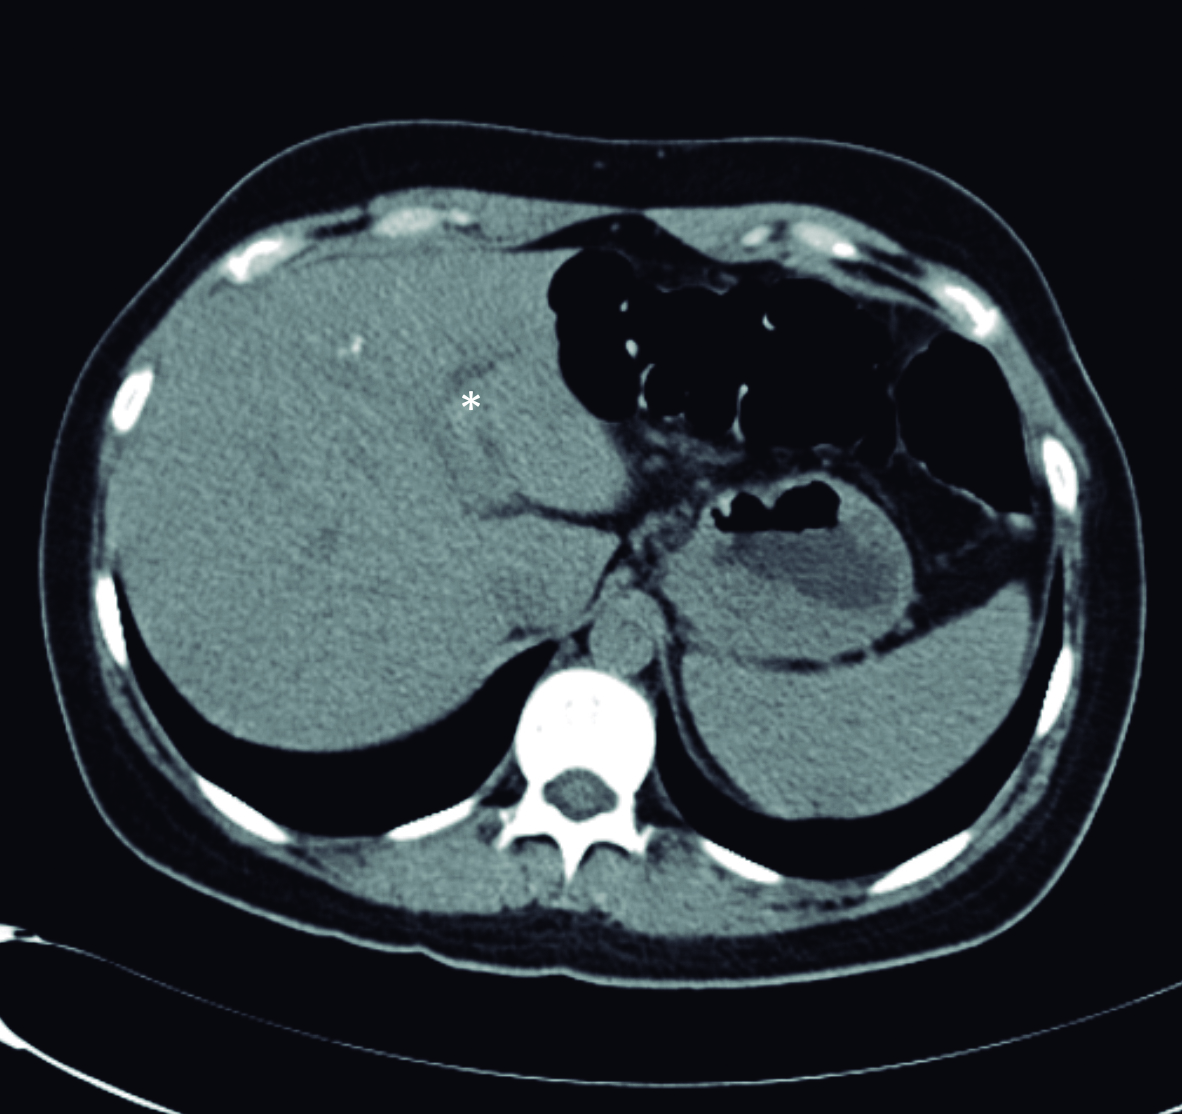

Una semana después se realiza ecoendoscopía digestiva alta, la cual informa colédoco de 9 mm de diámetro, en cuyo interior se observan dos líneas hiperecoicas alargadas, paralelas de unos 3 mm de diámetro total, compatible con Ascaris (Fig. 3).

Figura 3. Ecoendosopía

a y b) Líneas hiperecoicas alargadas, paralelas de 3 mm de diámetro compatible con Ascaris (mano).